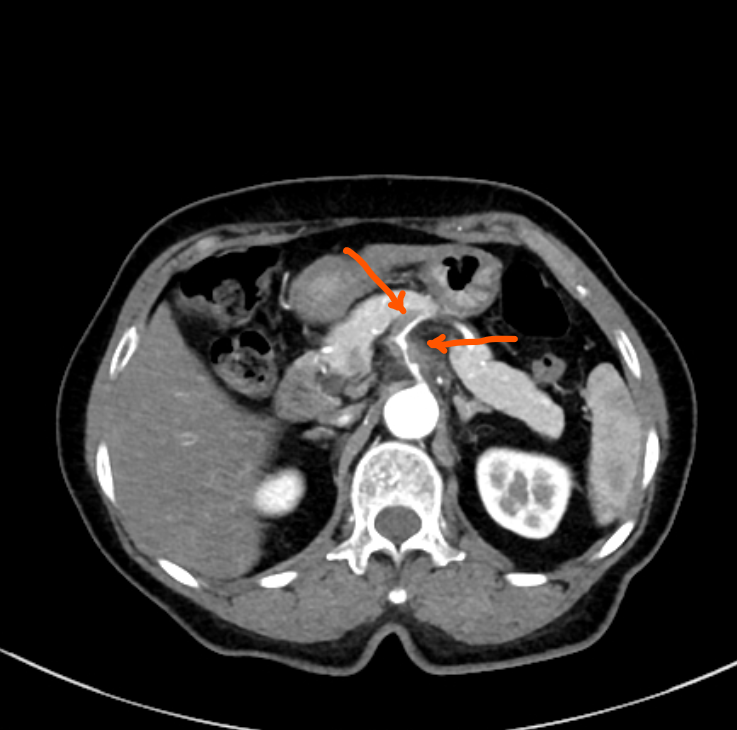

腹主动脉及双侧髂总动脉、髂内动脉管壁不光整,可见钙化斑块形成,双侧髂内动脉管腔轻度狭窄;腹主动脉分支腹腔干、肠系膜上动脉、肠系膜下动脉及双肾动脉开口自然,腹腔干及脾动脉起始处增粗,管壁增厚、毛糙,内见片状低密度充盈缺损,周围脂肪间隙模糊,腹腔干管腔重度狭窄,脾动脉起始处中度狭窄;肠系膜上动脉起始处管壁内膜增厚,管腔轻度狭窄;右肾动脉起始处管壁钙化斑块,管腔轻微狭窄;左肾动脉管壁规整,内膜未见增厚,管腔未见狭窄及扩张。

1.考虑腹腔干及脾动脉起始处夹层,伴腹腔干管腔重度狭窄,脾动脉起始处中度狭窄,建议治疗后复查。

腹腔干及脾动脉起始处夹层

增强可见动脉管腔的扩张,内膜片撕裂形成充盈缺损影,可见管腔分割成双腔或多腔,假腔为动脉内膜外侧形成的腔,与中膜分离的内膜位于真假腔之间,形成内膜片。假腔内血流较慢,增强动脉期密度常常低于真腔。管腔扩张,呈双腔改变,假腔呈“新月形”包绕真腔。假腔内如有血栓形成,则表现为“新月形”低密度影。真假腔之间为内膜片。